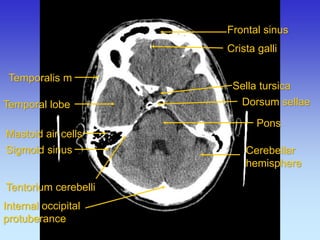

Crista galli

Temporalis m

Temporal lobe

Cerebellar hemisphere

Sigmoid sinus

Frontal sinus

Pons

Mastoid air cells

Dorsum sellae

Internal occipital protuberance

Tentorium cerebelli

Sella tursica